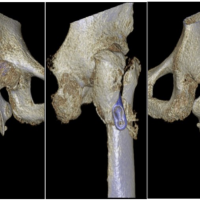

A 60-year-old female with osteoporosis sustained a displaced Garden’s type IV, Pauwel’s type III fracture. The fracture was fixed in neutral position with the FNS device, but the bolt and anti-rotation screw were placed too anteriorly, leaving a superolateral void at the head–neck junction. Although union was achieved at 5 months, the fracture underwent varus collapse and significant neck shortening, with radiographs showing a widening gap between the plate and lateral femoral cortex compared to immediate post-operative images (Fig. 6). This case emphasizes the importance of central implant positioning and valgus fixation in osteoporotic bone and perhaps a lower threshold for choosing replacement over fixation in osteoporotic bone.

Figure 6 Top left: Pre-operative radiographs of Case 7; top center: immediate post-operative AP radiograph of the fracture; top right: union with a shortened neck and varus collapse. Bottom left: Pre-operative radiograph of Case 8; bottom center: Intraoperative C-arm images following reduction to neutral- clearly showing a supero-lateral bony void; bottom right: varus collapse and neck shortening noticed at 7 months.

Case 8

A 66-year-old female sustained a valgus-impacted Garden’s type I, Pauwel’s type I fracture. During fixation, an attempt was made to correct the valgus to a neutral position, which created a superolateral void and reduced anti-rotation screw purchase. This destabilized the lateral hinge and predisposed the fracture to collapse. By 7 months, the fracture underwent varus collapse and shortening, evident from reduced space between the lateral end of the bolt and barrel compared to immediate post-operative images (Fig. 6). In hindsight, in situ fixation or valgus fixation would likely have been preferable in such cases.